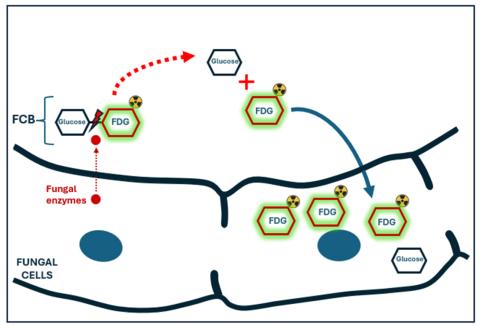

“The idea of cellobiose, which is composed of two glucose molecules bound together, is really cool,” Hammoud elaborated. “In real life, only certain fungi can produce the special enzymes needed to break the bond between the two glucose molecules of cellobiose. Those enzymes are not present in bacteria or in mammalian cells. By adding a radioactive tag to cellobiose and exposing it to fungal infection, such as Aspergillus, the sugar is broken into two molecules which are then taken inside the fungus. This results in accumulation of the radioactive signal in the infection.

“If there is no fungus, on the other hand, cellobiose remains intact and is eventually excreted by the kidneys with no residual radioactive signal in the body.”